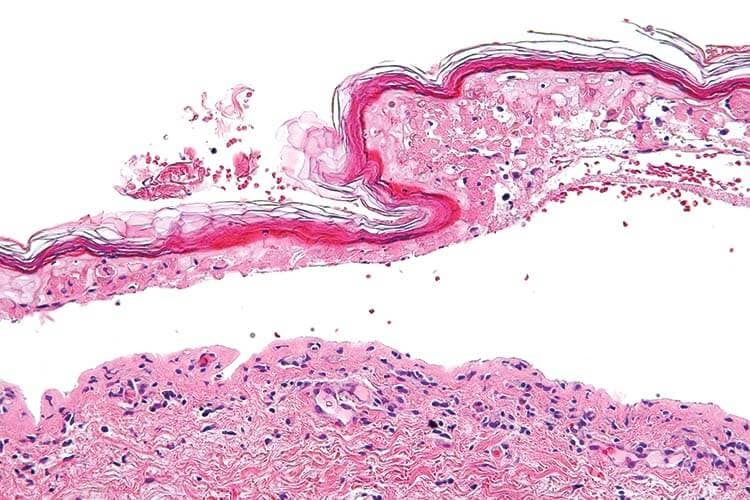

Die Arzneimittelexanthem-Formen des Stevens-Johnsons-Syndrom bzw. der toxischen epidermalen Nekrolyse (TEN) gehen mit einer subepidermalen Spaltbildung zwischen Epidermis und Dermis einher.

- Staphylogene toxisch epidermale Nekrolyse (SSSS): Die Spaltbildung erfolgt subkorneal und betrifft weniger tiefer liegende subepidermale Schichten. Das Nikolski-Zeichen ist häufig positiv, bei sehr oberflächlicher Hautablösung jedoch "trocken".

Im Durchschnitt liegen ein bis vier Wochen zwischen der Einnahme und dem Auftreten der Hautreaktionen. Zur Abklärung, insbesondere bei schweren Reaktionen, empfiehlt die Expertin eine histologische Untersuchung, bei der die charakteristischen nekrotischen Keratinozyten auffallen. Die Angst vor einer störenden Narbe durch die Biopsie wiegt weniger schwer als die Gefahr einer Fehldiagnose. Die Letalität der toxischen epidermalen Nekrolyse liegt bei etwa sechs Prozent.